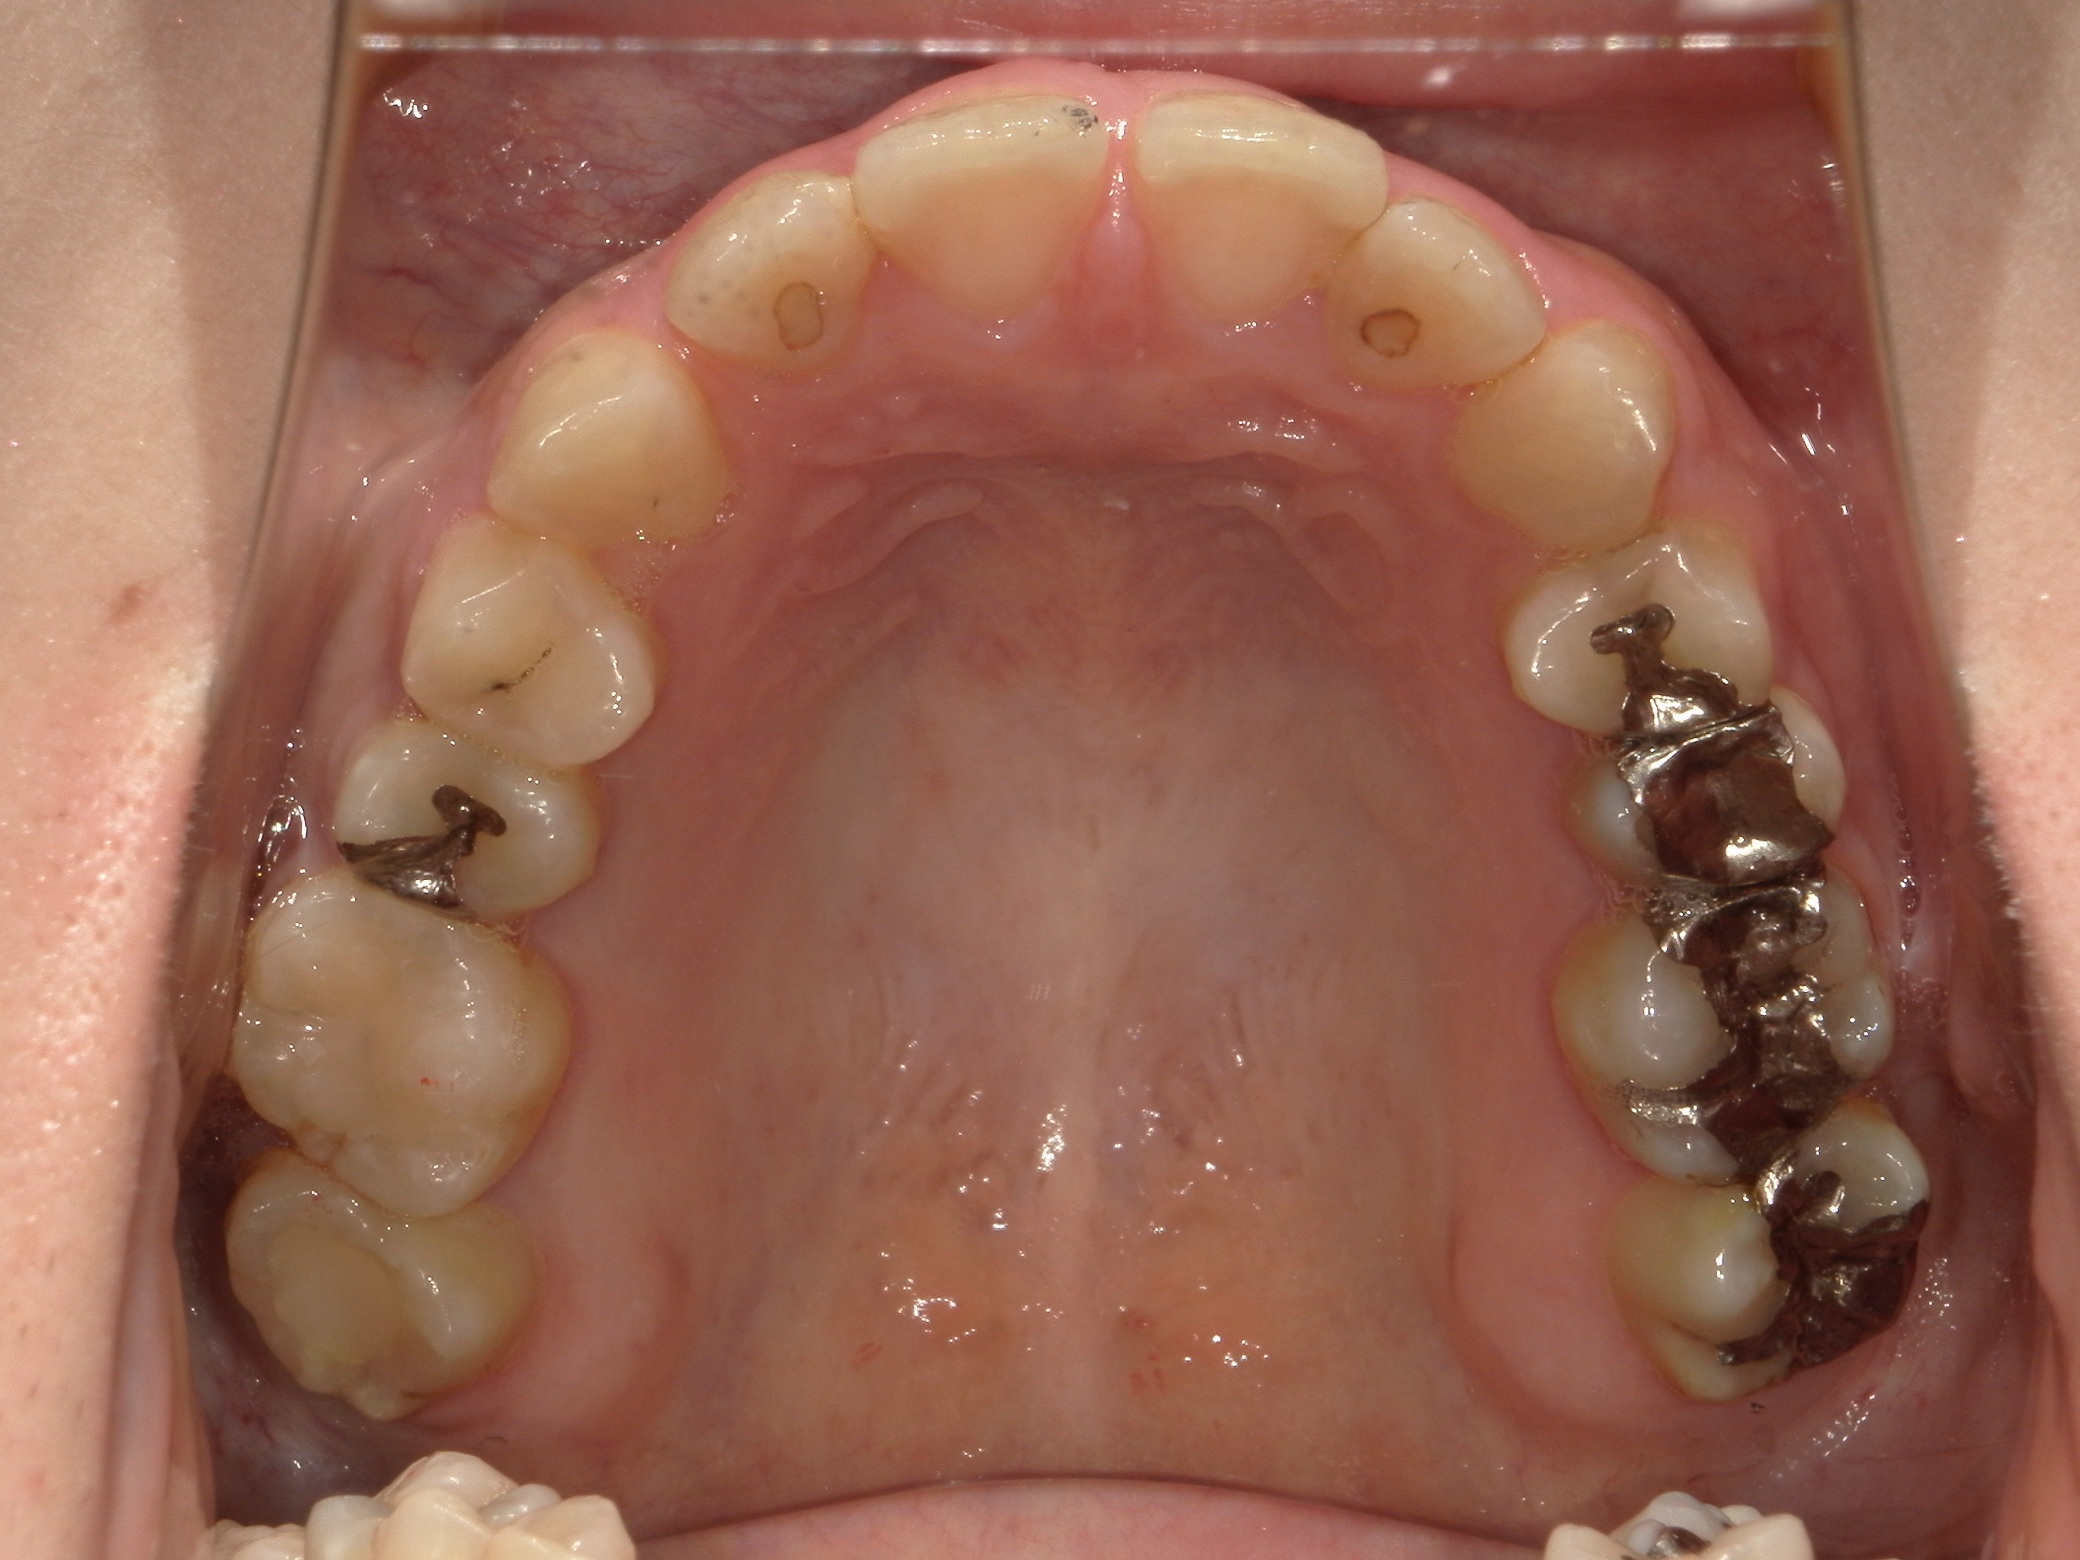

口内上

治療前

治療後